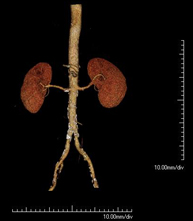

Prova diagnòstica no invasiva que consisteix en l'estudi de l'artèria aorta abdominal a través de l'obtenció d'imatges d'alta definició anatòmica mitjançant l'ús d'un equip de TC (Tomografia Computeritzada) i de contrast iodat. La qualitat de les imatges permet realitzar reconstruccions en 2D i 3D gràcies a estacions de treball especialitzades en l'estudi arterial. Està indicat en aquells pacients amb malaltia vascular (arteriosclerosi), en aneurismes d'aorta, en pacients amb dolor abdominal de possible origen vascular, en estudis prequirúrgics de lesions adjacents a l'aorta abdominal com a "mapa" vascular. La informació obtinguda de manera no invasiva és indispensable per als pacients que requereixen tractament percutani o quirúrgic. En aquells pacients que només requereixen seguiment de les lesions vasculars, aquesta tècnica és la tècnica no invasiva d'elecció juntament amb l'angio-RM. - Angio-TC Artèries renals

Prova diagnòstica no invasiva que consisteix en l'estudi de les artèries renals a través de l'obtenció d'imatges d'alta definició anatòmica mitjançant l'ús d'un equip de TC (Tomografia Computeritzada) i de contrast iodat. La qualitat de les imatges permet realitzar reconstruccions en 2D i 3D gràcies a estacions de treball especialitzades en l'estudi arterial. Està indicat en aquells pacients amb malaltia vascular (arteriosclerosi), en aneurismes d'aorta, en pacients amb dolor abdominal de possible origen vascular, en estudis prequirúrgics de lesions adjacents a l'aorta abdominal com a "mapa" vascular. La informació obtinguda de manera no invasiva és indispensable per als pacients que requereixen tractament percutani o quirúrgic. En aquells pacients que només requereixen seguiment de les lesions vasculars, aquesta tècnica és la tècnica no invasiva d'elecció juntament amb l'angio-RM. - Angio-TC Aorto-ilíac

Prova diagnòstica no invasiva que consisteix en l'estudi de les artèries ilíaques i l'aorta abdominal a través de l'obtenció d'imatges d'alta definició anatòmica mitjançant l'ús d'un equip de TC (Tomografia Computeritzada) i de contrast iodat. La qualitat de les imatges permet realitzar reconstruccions en 2D i 3D gràcies a estacions de treball especialitzades en l'estudi arterial. Aquesta prova està especialment indicada com estudi prequirúrgic (mapa vascular) abans d'intervencions percutànies o quirúrgiques d'aorta abdominal, com l'estudi complementari en pacients amb isquèmia de membres inferiors, etc. - Colonoscòpia virtual

Prova diagnòstica no invasiva que consisteix en l'estudi de l'artèria aorta abdominal amb l'obtenció d'imatges d'alta definició anatòmica mitjançant l'ús d'un equip de TC (Tomografia Computaritzada) i contrast iodat. La qualitat de les imatges permet realitzar reconstruccions en 2D i 3D gràcies a estacions de treball especialitzades en l'estudi arterial. Està indicat en aquells pacients que pateixen malaltia vascular (arteriosclerosi), aneurismes d'aorta, en pacient amb dolor abdominal d'un possible origen vascular, en estudis prequirúrgics de lesions adjacents a l'aorta abdominal com el "mapa" vascular, etc. La informació obtinguda de forma no invasiva és indispensable per als pacients que requereixen tractament percutani o quirúrgic. En aquells pacients que només requereixen un seguiment de les lesions vasculars, aquesta tècnica és la tècnica no invasiva d'elecció juntament amb l'angio RM. - Angio TC d'artèries renals

Prova diagnòstica no invasiva que consisteix en l'estudi de les artèries renals amb l'obtenció d'imatges d'alta definició anatòmica mitjançant l'ús d'un equip de TC (Tomografia Computaritzada) i contrast iodat. La qualitat de les imatges permet realitzar reconstruccions en 2D i 3D gràcies a estacions de treball especialitzades en l'estudi arterial. Aquesta prova està indicat en aquells pacients que pateixen HTA refractària al tractament, en pacients amb lesions renals que tenen un mapa vascular prequirúrgic, etc. - Angio TC d'aorta-ilíaca

Prova diagnòstica no invasiva que consisteix en l'estudi de les artèries ilíaques i l'aorta abdominal amb l'obtenció d'imatges d'alta definició anatòmica mitjançant l'ús d'un equip de TC (Tomografia Computaritzada) i contrast iodat. La qualitat de les imatges permet realitzar reconstruccions en 2D i 3D gràcies a estacions de treball especialitzades en l'estudi arterial. Aquesta prova està especialment indicada com a estudi prequirúrgic (mapa vascular) abans d'intervencions percutànies o quirúrgiques d'aorta abdominal, estudi complementari en pacients amb isquèmia de membres inferiors, etc. - Angio TC arterial d'extremitats inferiors